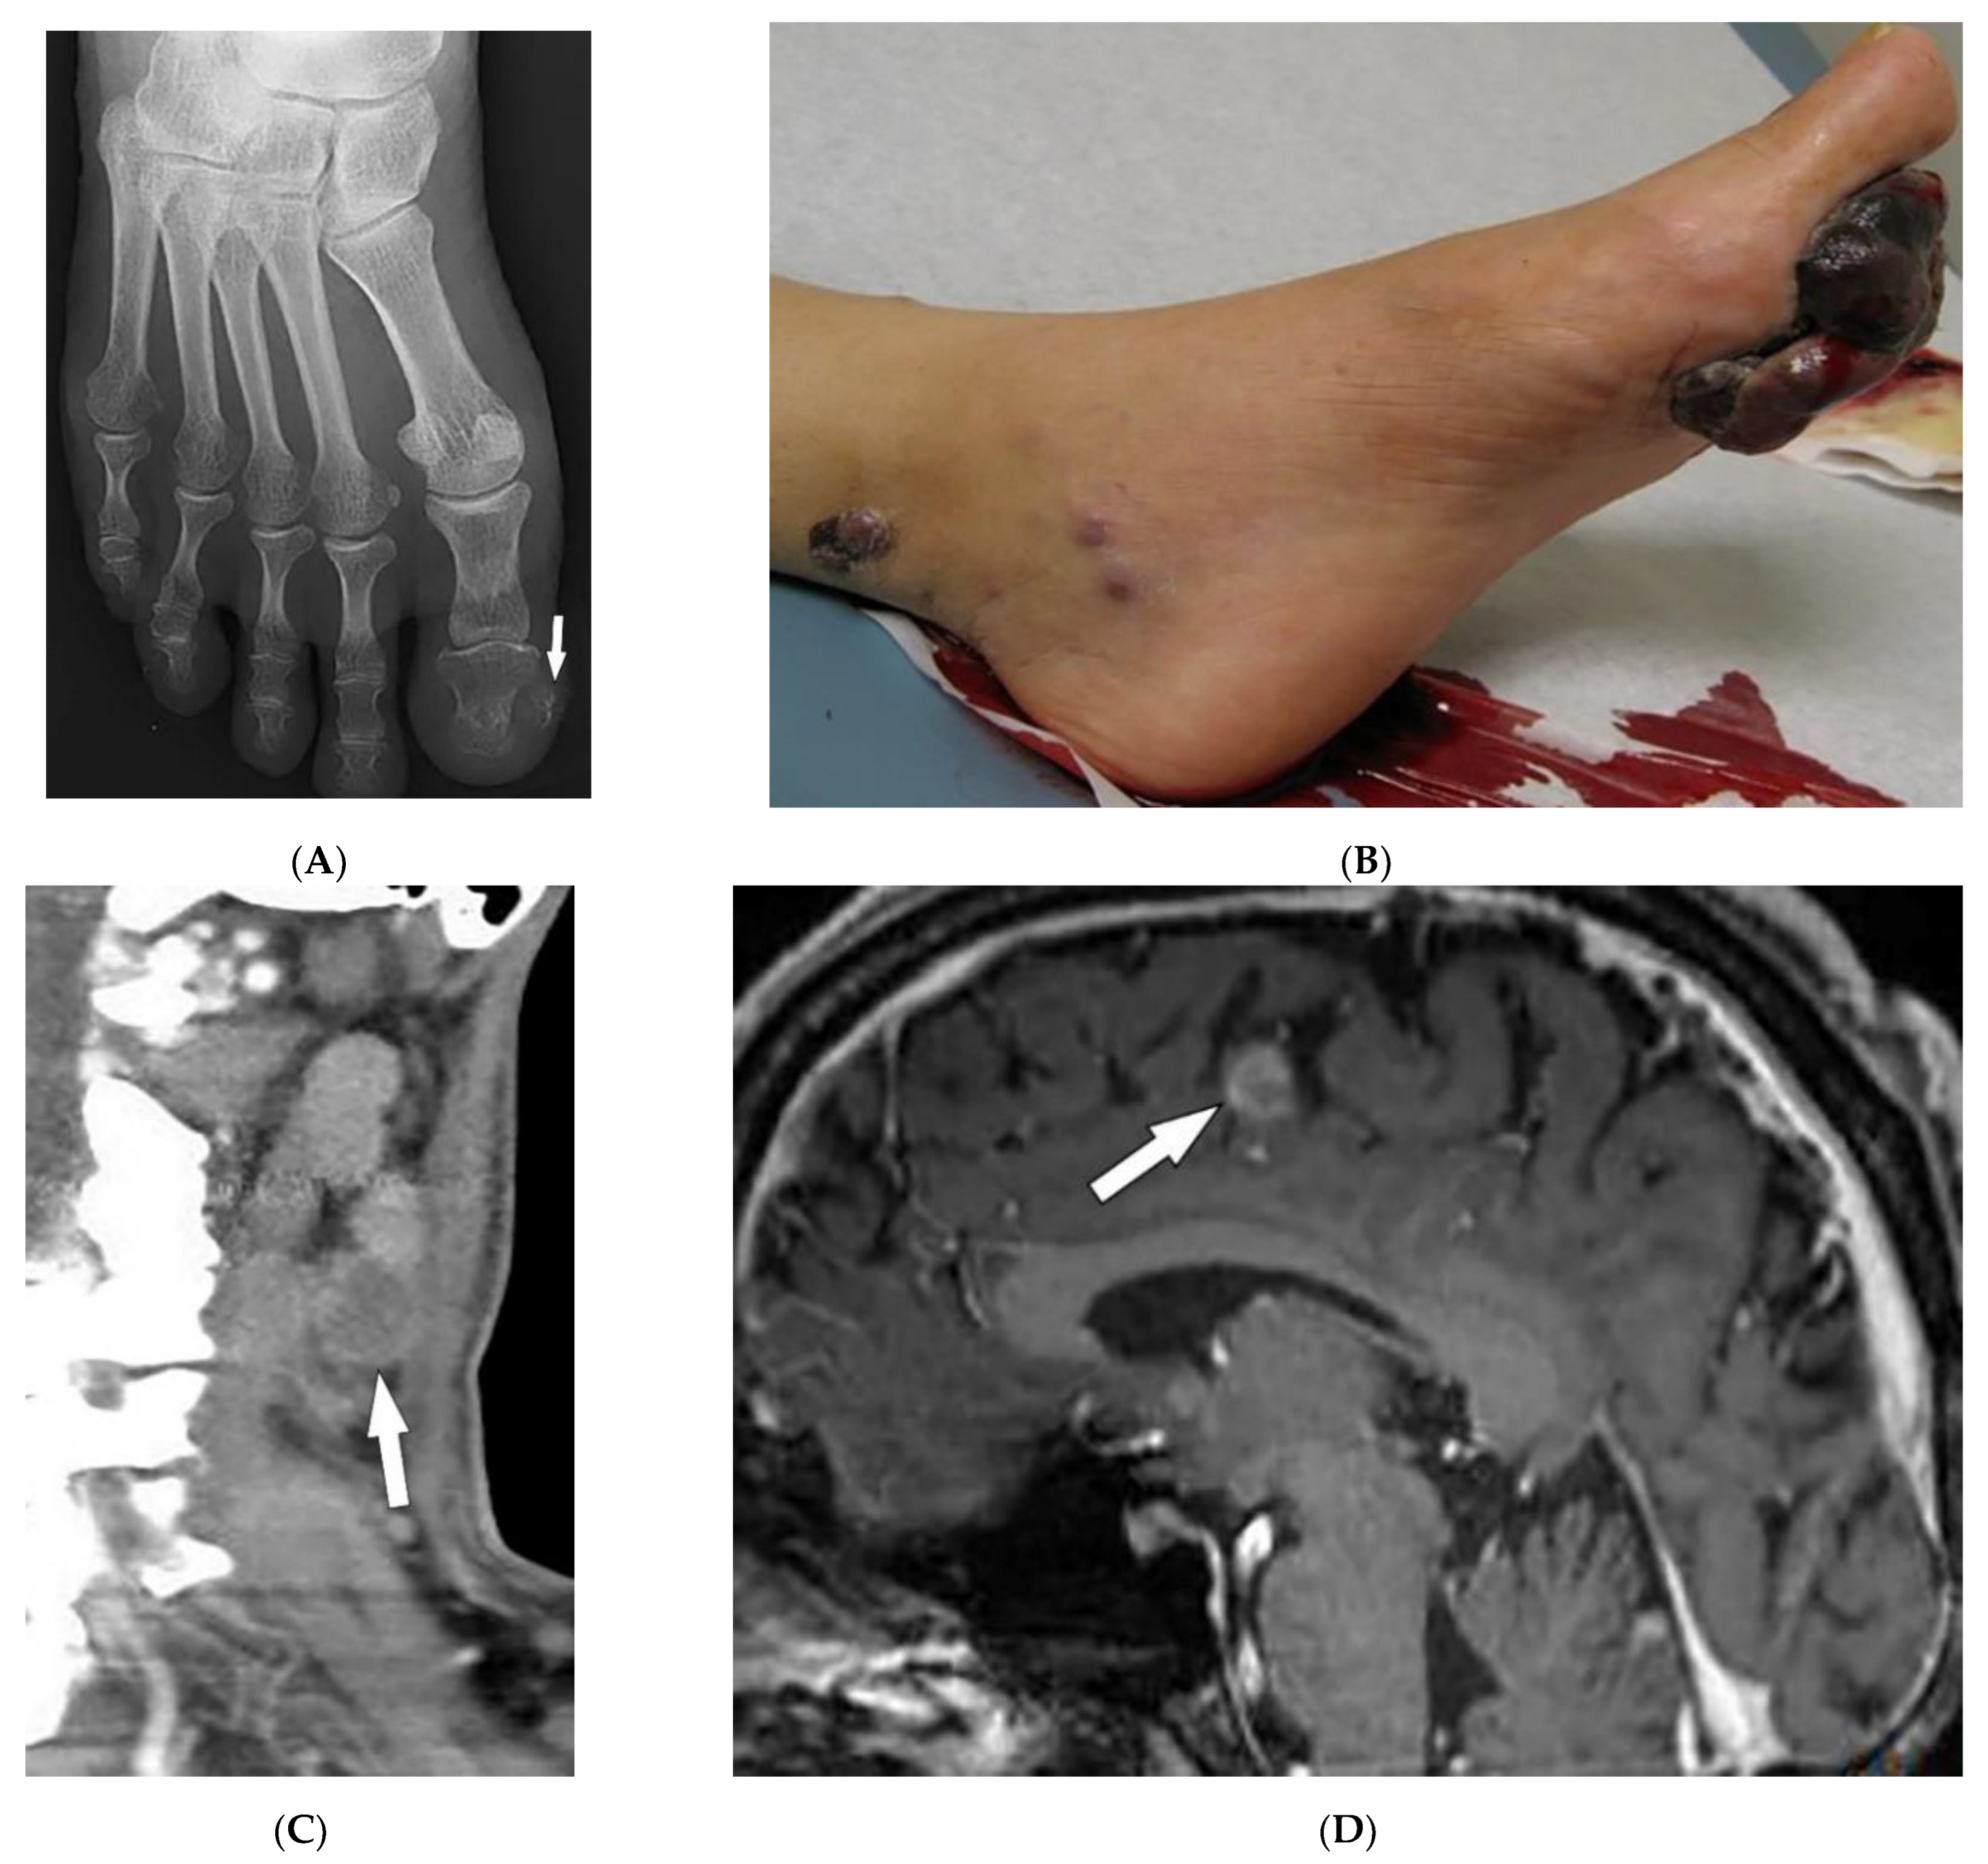

4.2. Kaposi Sarcoma

| Kaposi sarcoma | Erythematous or violaceous macules, plaques, nodules Pulmonary involvement Gastrointestinal involvement | Nodular enhancing masses Peribroncovascular nodules and halo sign |